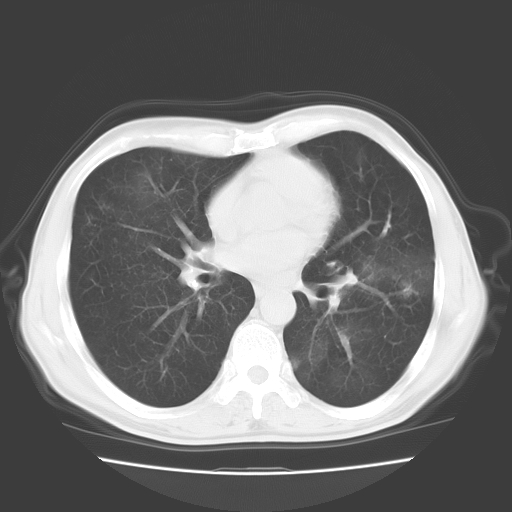

以下是引用随光逐影在2008-11-20 23:02:00的发言:[br]1)考虑左肺上叶周围型肺癌可能性大。2)两肺散在性肺泡积血。[br][br][本贴已被 随光逐影 于 2008-11-20 23:09:31 修改过]

以下是引用drzhang8888在2008-11-20 22:20:00的发言:[br]密集的短毛刺,血管集束,胸膜凹陷,周边型肺癌可能性大,另双肺多发磨玻璃影,考虑感染

以下是引用流浪星在2008-11-20 22:28:00的发言:[br]左肺上叶近外围区见一类圆形结节影,毛刺征、胸膜尾征阳性,临近肺组织见多发渗出灶。考虑1,炎症性病变。 2.周围性肺癌。建议抗炎治疗后复查。

以下是引用qc80012345在2008-11-21 5:53:00的发言:[br]支持;周围型肺癌诊断。增强扫描。